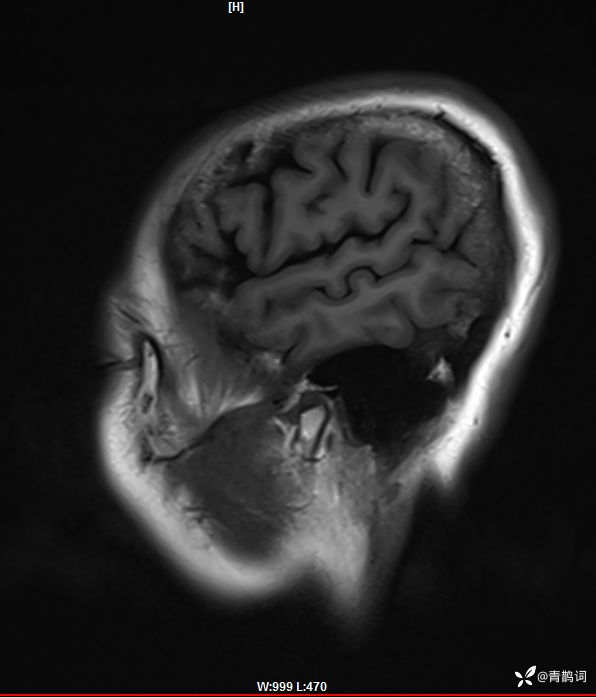

病例分享 | 45岁女患,7年的病史,结合影像学,如何诊断?

1、患者:女, 年龄:45岁

2、主诉:走路不稳渐加重7年,饮水呛咳伴头晕2年渐加重。

3、简要病史:患者于入院前7年出现走路不稳,表现为行走右偏,逐渐加重,易跌倒、不能自理;近2年出现饮水呛咳、吞咽困难及头晕;病程伴有耳鸣、反应迟钝,无恶心、呕吐。既往否认高血压、否认糖尿病、否认冠心病。

4、体格检查:体温36.0℃,脉搏80次/分,呼吸20次/分,血压140/70mmHg。查体:神清,构音障碍;眼球运动自如,双水平性眼震,左视时明显;双侧瞳孔等大同圆,左:右=3mm:3mm,对光反射灵敏;双侧额纹对称,双侧鼻唇沟对称;伸舌居中;四肢肌力4级,肌张力减低,四肢腱反射亢进,双侧Babinski征阳性;粗测感觉未见明显异常;四肢共济运动完成差,左侧为著;脑膜刺激征阴性。

入院后完善磁共振:

矢状位: